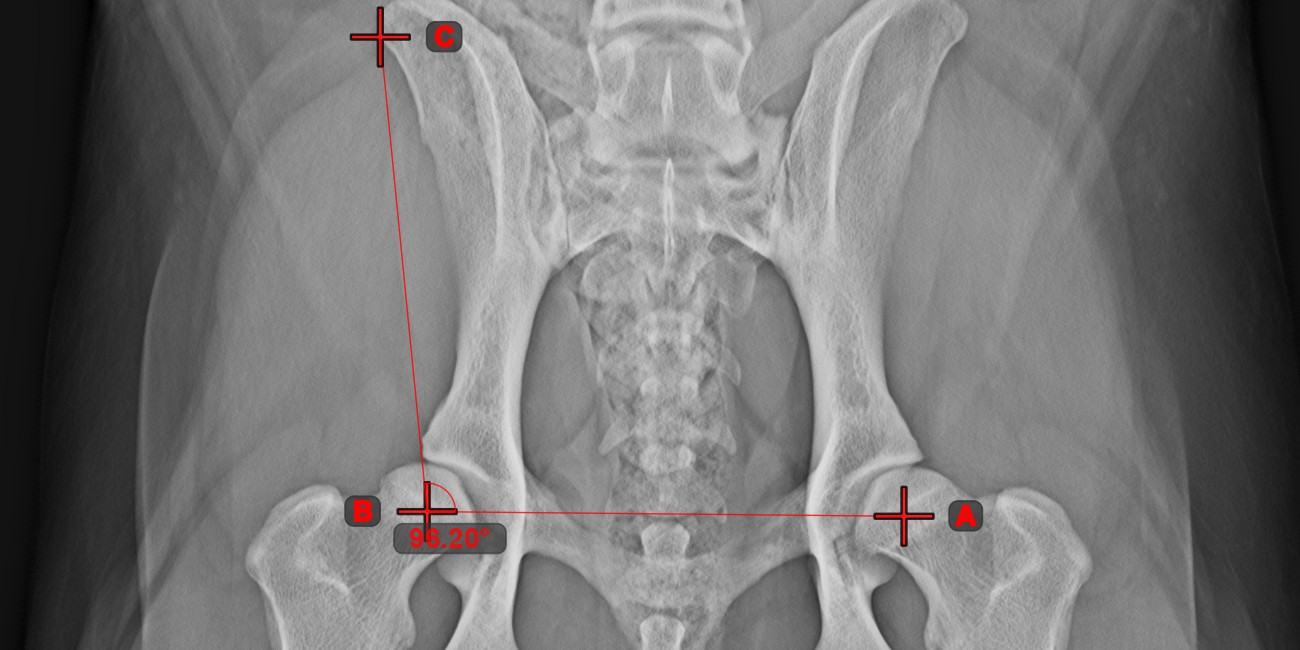

Vonalak szöge¶

Válassza ki az eszközt a bal oldali eszköztárból, és rendelje hozzá az egyik elérhető egérgombhoz. A jelenetben már meglévő vonalak közül kezdje az első vonal kiválasztásával , vagy helyezze el a kezdő- és végpontot a vonal létrehozásához. Ismételje meg ugyanezeket a lépéseket a mérés második vonalánál. A két vonal közötti szög automatikusan kiszámításra kerül.

Módosítsa mindkét vonal kezdő- és végpontját az Elem kiválasztása/mozgatása eszközzel. A két vonal közötti szöget automatikusan újrakalkulálja a rendszer.

Információ

Ha két vonal közvetlenül nem metszi egymást a jeleneten, azok meghosszabbított vetületeinek szöge kerül kiszámításra.